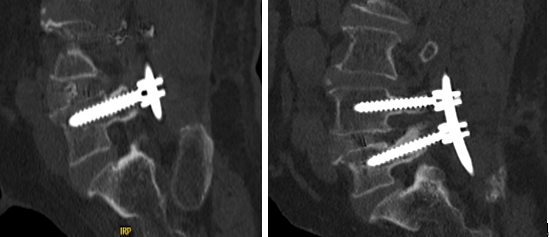

手术后进行CT复查,螺钉与术前规划完全一致。而对于李大爷这样的老年人术后常出现的由于气血瘀滞所导致腹胀、便难、失眠等问题,浙江省中医院骨伤科又采用了身痛逐淤汤活血化瘀、祛风止痛,配合艾灸、腕踝针、耳穴压豆等传统中医外治方式,帮助李大爷早期快速恢复。术后仅2天,李大爷即自行下地站立。

钱宇教授介绍,OLIF手术已经在浙江省中医院常规开展。脊柱手术机器人可以通过术前规划,精准模拟术中各种内植物的置入轨迹,在经皮椎弓根螺钉植入、椎间孔镜手术定位穿刺、经皮球囊扩张手术穿刺等操作中提供实时引导,尤其在风险更高的胸椎或脊柱畸形等手术中,缩短手术时间。两种微创技术的融合,避免原本需要大切口的传统手术方式。